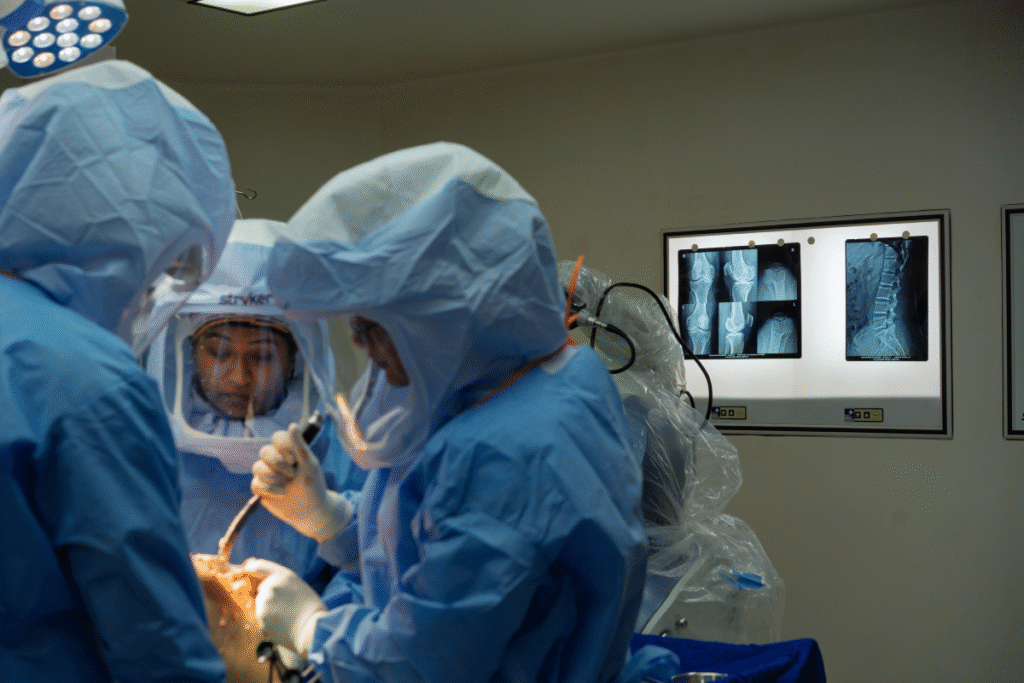

Step 3: The Surgery

On the day of surgery, the operation usually takes about 1 to 2 hours depending on complexity.

Anesthesia: You will receive either general anesthesia (sleep) or regional/spinal anesthesia (numbing from waist down) plus pain control medications.

Incision and Preparation: An incision is made over the hip. Damaged cartilage and bone of the hip joint (femoral head and acetabulum) are removed.

Implant Placement: A metal stem is placed into the thigh bone (femur), a metal or ceramic ball replaces the femoral head, and a new socket (cup) is fixed into the pelvis. A plastic, ceramic, or metal liner is inserted to allow smooth movement.

Closure: The incision is closed with sutures or staples and a sterile dressing is applied.